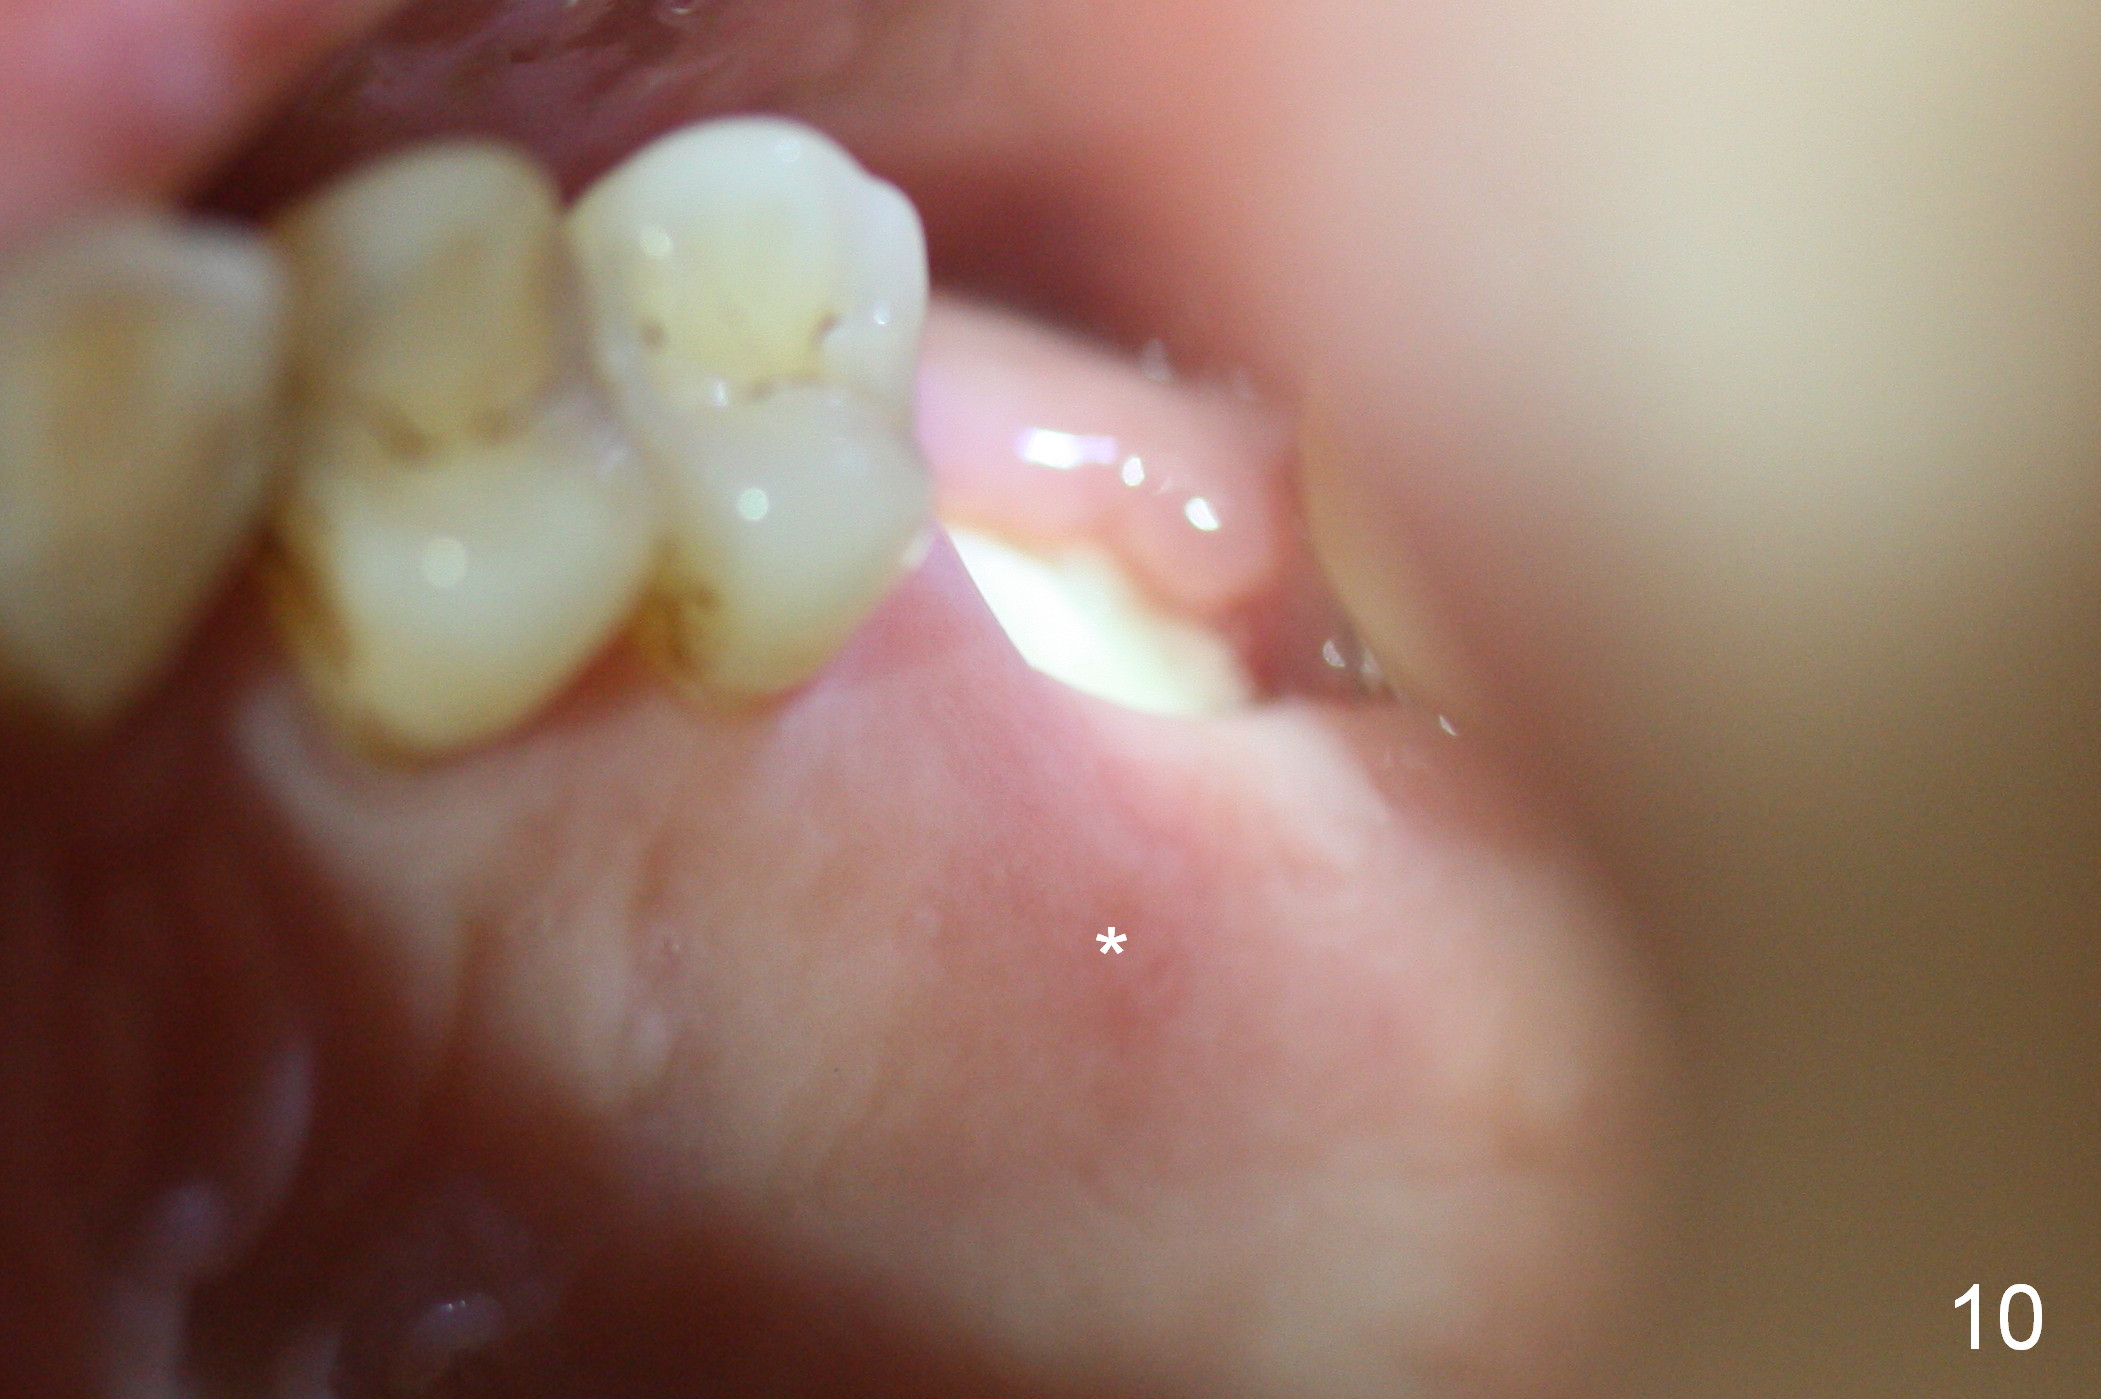

There is no palatal erythema or edema 9 days post extraction (Fig.10 *) with shrinkage of the socket opening. The Osteogen plug remains in place (Fig.11 P). The patient will return for implant placement 6 months post socket preservation.